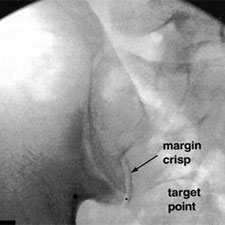

El punt negre visualitza el target on practicar la infiltració. La interlínia assenyalada es refereix a la part posterior de l'articulació.